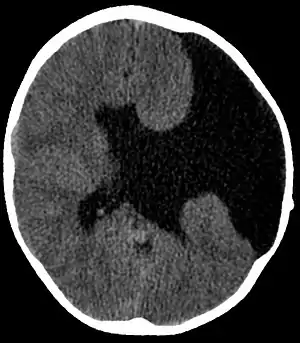

| Axial CT scan showing schizencephaly in a 6-year-old child | |

Schizencephaly (from Greek skhizein 'to split', and enkephalos 'brain')[1][2] is a rare birth defect characterized by abnormal clefts lined with grey matter that form the ependyma of the cerebral ventricles to the pia mater. These clefts can occur bilaterally or unilaterally. Common clinical features of this malformation include epilepsy, motor deficits, and psychomotor retardation.[3]

Schizencephaly can be distinguished from porencephaly by the fact that in schizencephaly, the fluid-filled component is entirely lined by heterotopic grey matter, while a porencephalic cyst is lined mostly by white matter. Individuals with clefts in both hemispheres, or bilateral clefts, are often developmentally delayed and have delayed speech and language skills and corticospinal dysfunction. Individuals with smaller, unilateral clefts (clefts in one hemisphere) may be weak or paralyzed on one side of the body and may have average or near-average intelligence. Patients with schizencephaly may also have varying degrees of microcephaly, Cognitive impairment, hemiparesis (weakness or paralysis affecting one side of the body), or quadriparesis (weakness or paralysis affecting all four extremities), and may have reduced muscle tone (hypotonia). Most patients have seizures, and some may have hydrocephalus.[4]